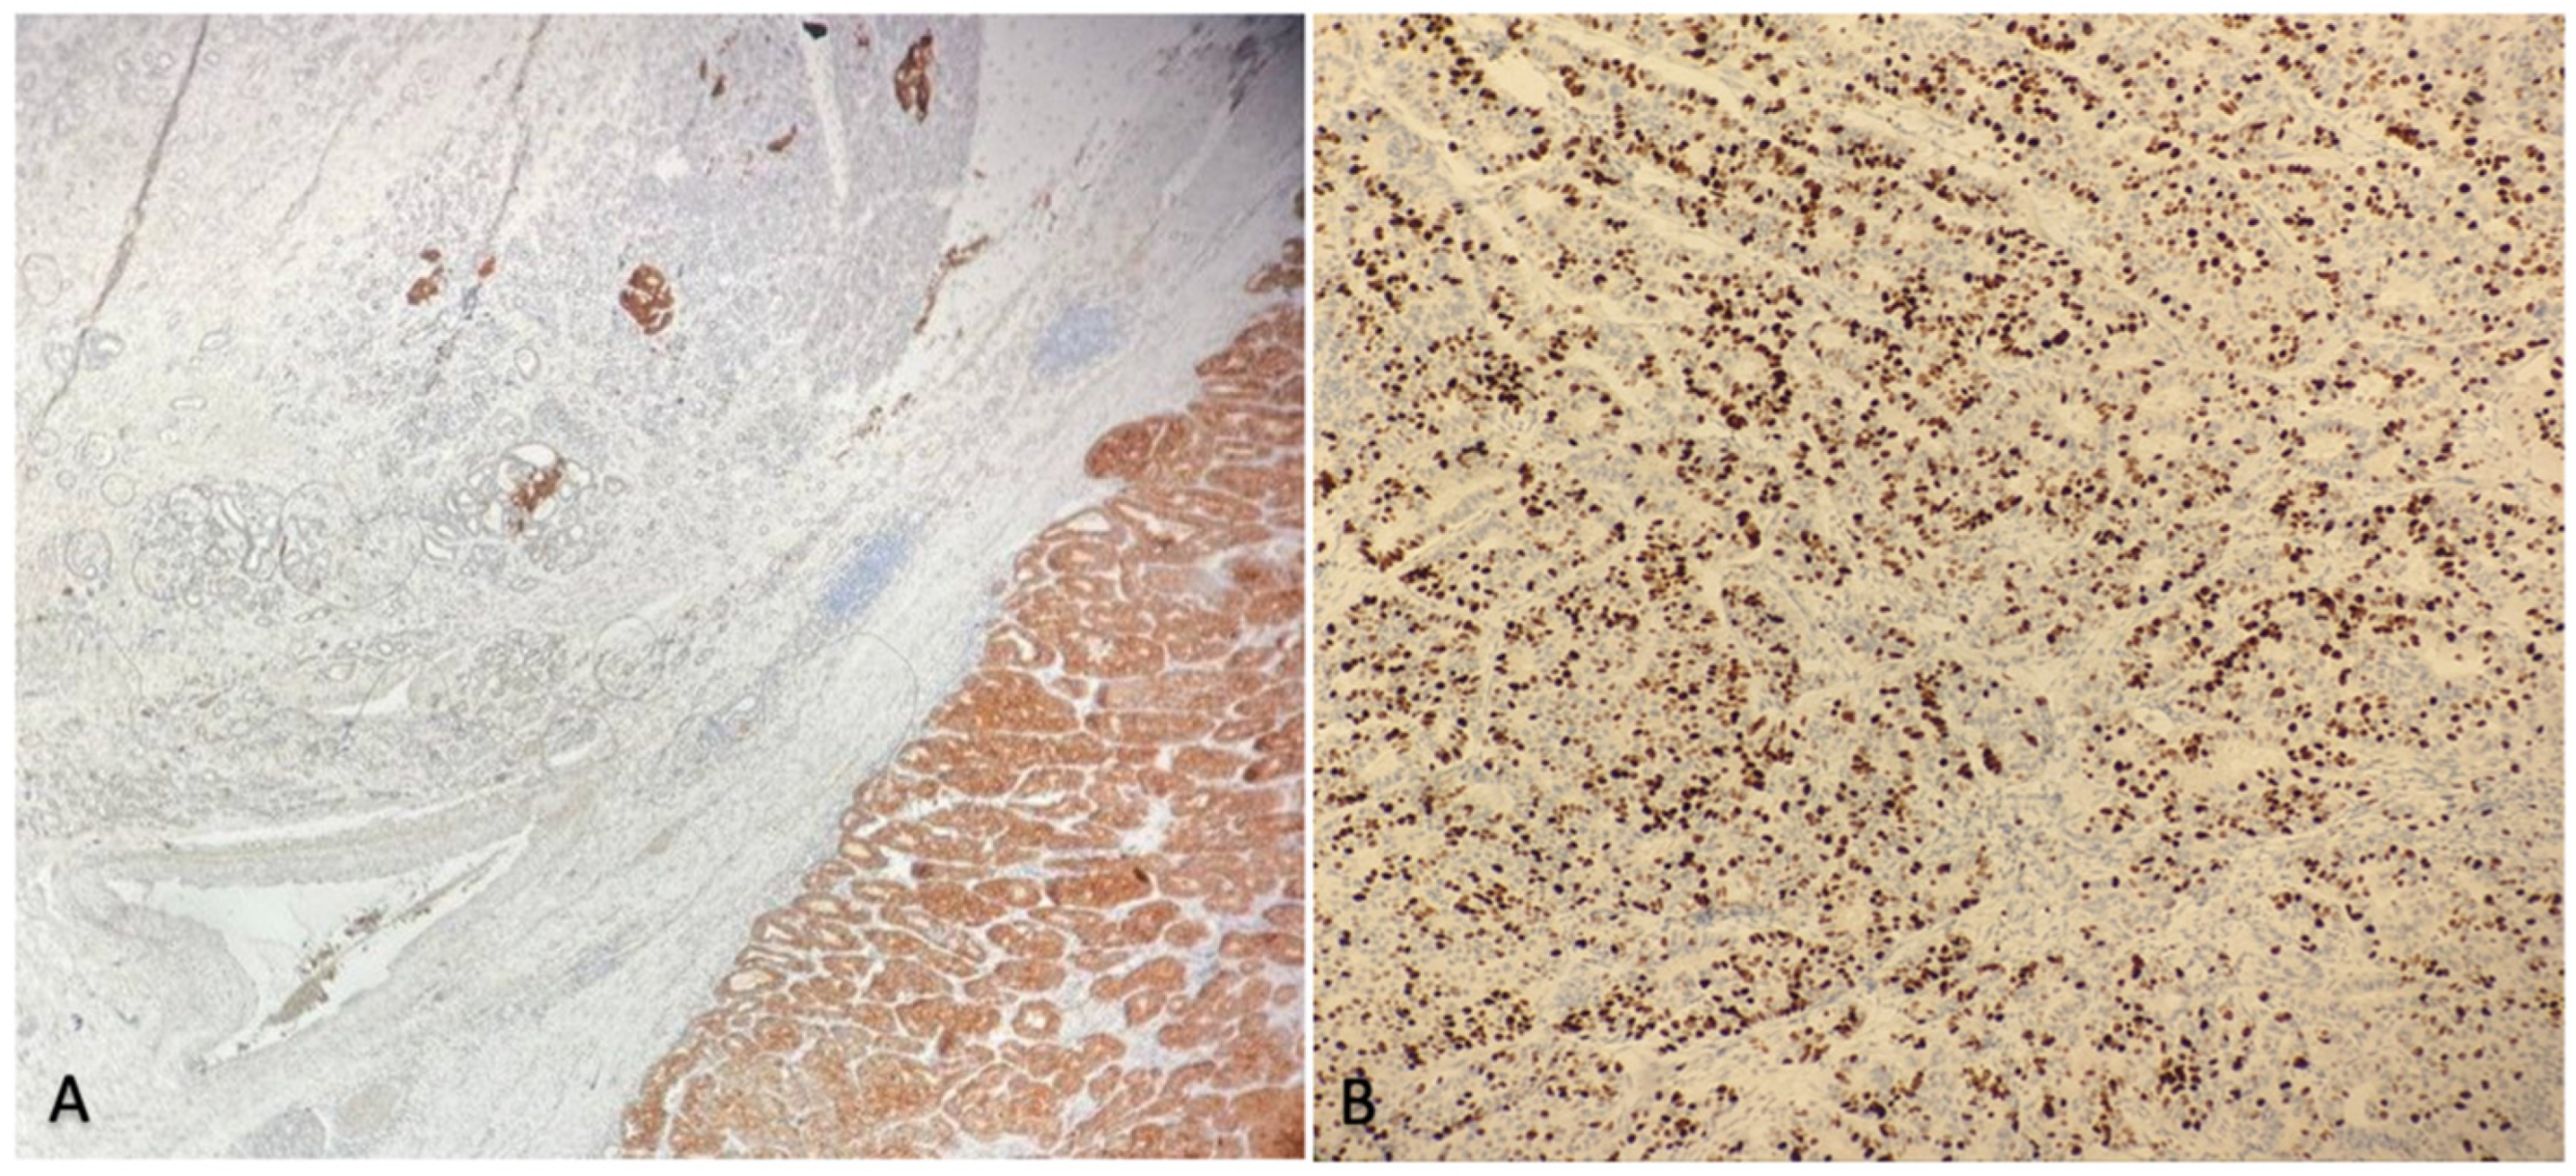

2.3. Histological Findings